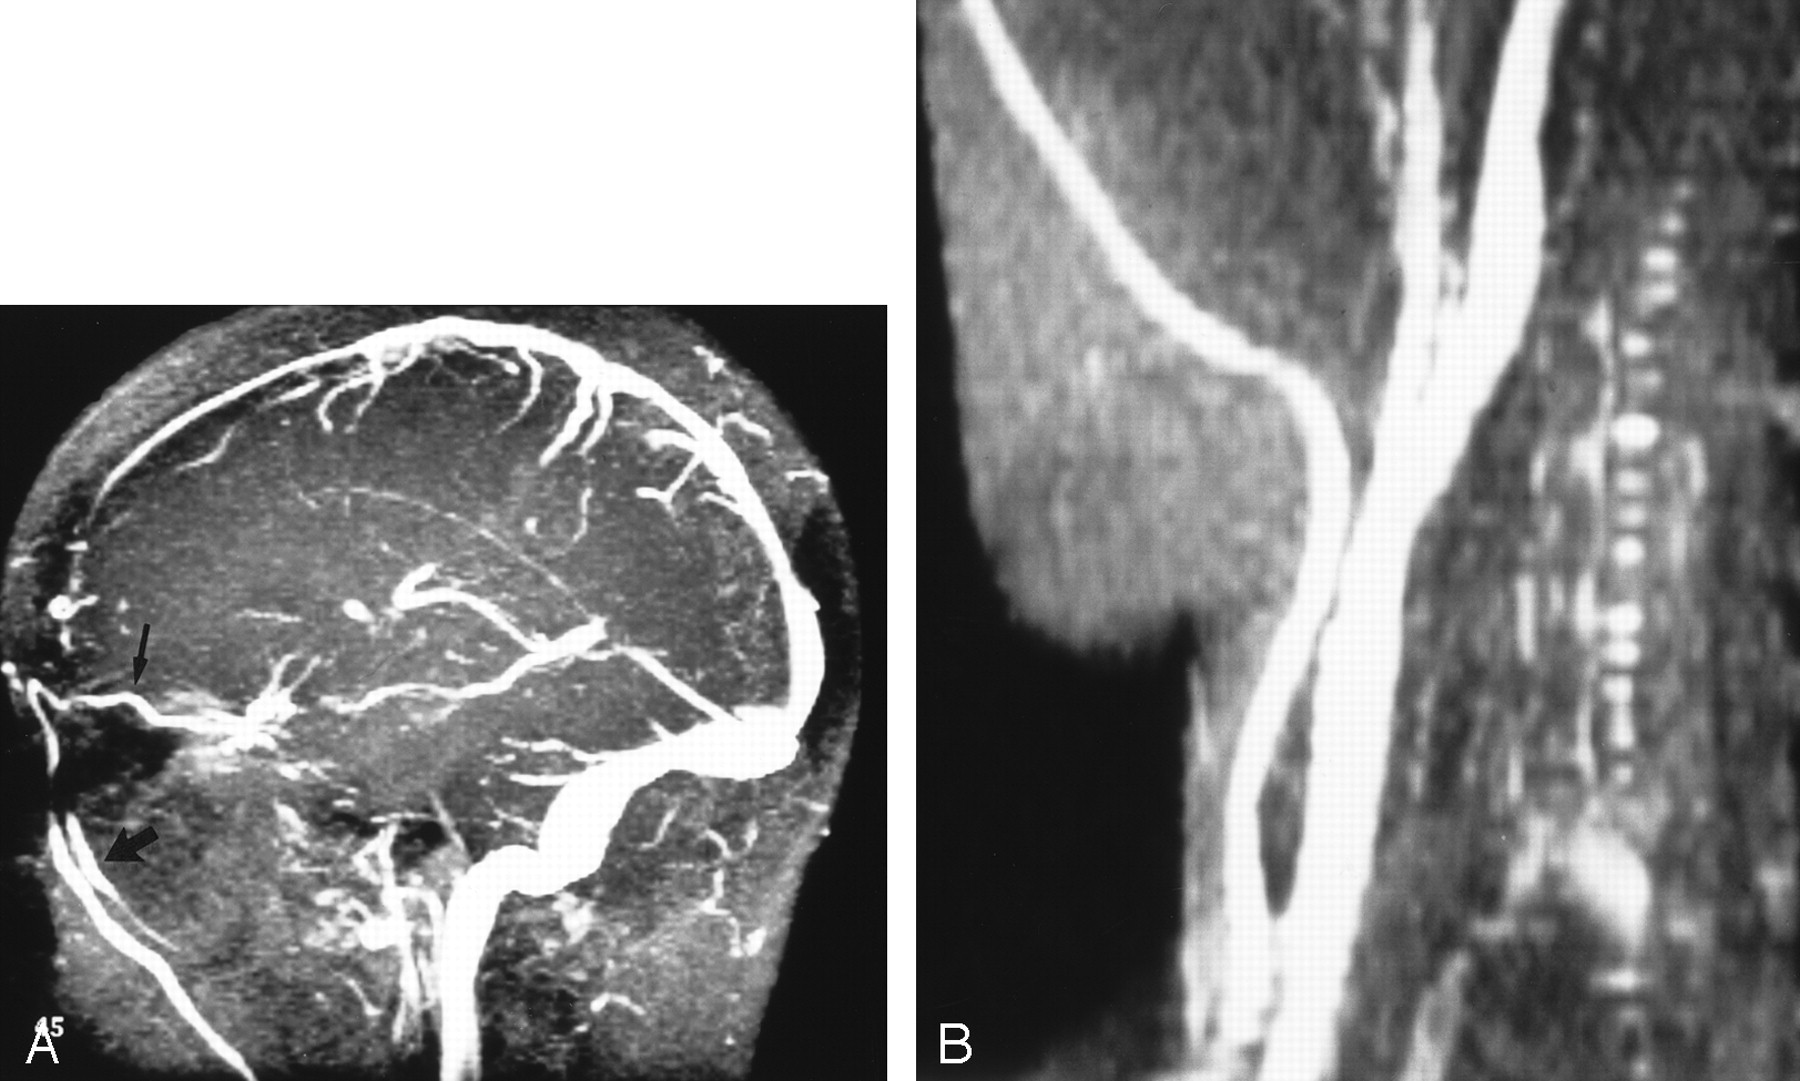

Figure 5A is the MR venogram obtained from a patient with IIH that shows extensive venous collateral flow through the orbits and face, and Figure 5B shows the distended great veins of the neck. The patient in Figure 5 was also noted to have iron deficiency anemia (hemoglobin 83 mg/L). Anemia would be expected to potentiate the hyperemia of IIH by producing an anoxic stress to the brain, further increasing the arteriolar relaxation. Treatment of iron deficiency anemia has resulted in resolution of the symptoms of IIH, and recurrence of IIH symptoms has occurred with relapse of anemia (1, 25).

Patient with IIH.

A, MR venogram (30/5/1 [TR/TE/NEX]) shows a dilated ophthalmic vein (thin arrow) leading to distended facial veins (thick arrow).

B, MR venogram (30/5/1) shows distended veins of the right side of the neck.